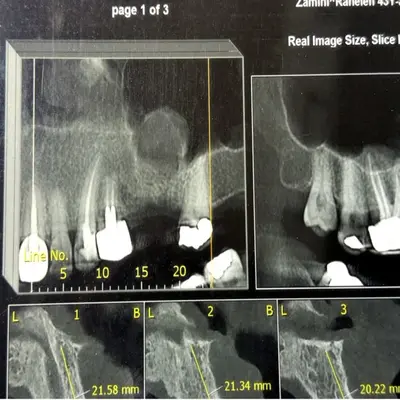

دندانهای عقل خارجشده با ریشه کامل کنار تصویر رادیوگرافی OPG